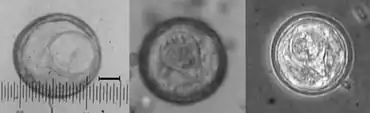

A Bertiella infection is typically diagnosed by observing eggs or proglottids in stool. They can be white, around 8 mm wide and 11 mm long, and moving. It can also be identified by presenting with common signs and symptoms in an area where disease is present, and there is close contact with soil and/or nonhuman primates. In many of these areas, other parasitic diseases can be a problem to the population, and finding the proglottids in stool samples can be the only way to distinguish Bertiella from other parasites. The appearance of the eggs has been described as "slightly oval and thin-shelled" while the "embryo is encased in a capsule or pyriform apparatus with two blunt horns."[1]